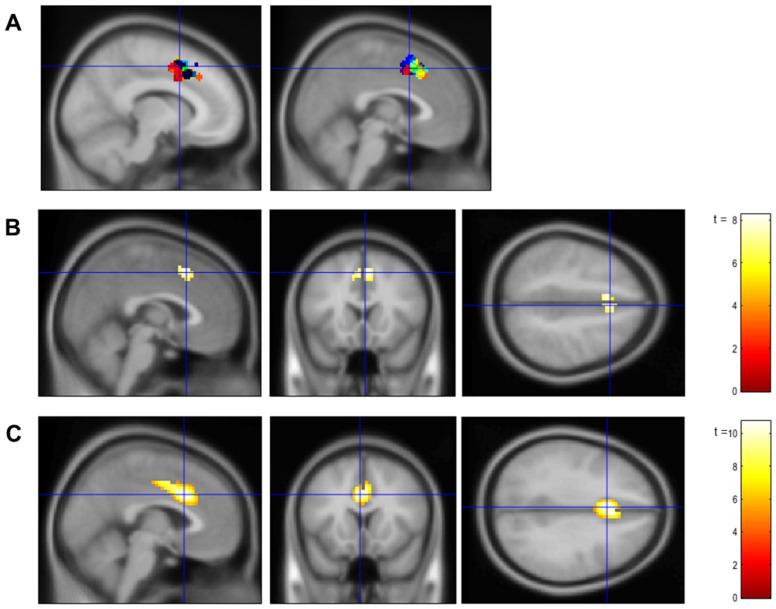

Selective attention declines with age, due to age-related functional changes in dorsal anterior cingulate cortex (dACC). Real-time functional magnetic resonance imaging (rtfMRI) neurofeedback has been used in young adults to train volitional control of brain activity, including in dACC.

METHODS

For the first time, this study used rtfMRI neurofeedback to train 19 young and 27 older adults in volitional up- or down-regulation of bilateral dACC during a selective attention task.

由于背侧前扣带回皮质(dACC)与年龄相关的功能变化,选择性注意力会随着年龄的增长而下降。实时功能磁共振成像(rtfMRI)神经反馈已被用于年轻人,以训练对大脑活动的意志控制,包括对dACC的控制。

方法

本研究首次使用rtfMRI神经反馈,在一项选择性注意力任务中,训练19名年轻人和27名老年人对双侧dACC进行意志性上调或下调。